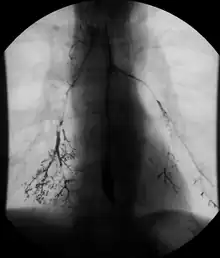

Normal barium swallow fluoroscopic image, showing the ingested barium sulfate being induced down the oesophagus by peristalsis. | |

An upper gastrointestinal series, also called a barium swallow, barium study, or barium meal, is a series of radiographs used to examine the gastrointestinal tract for abnormalities. A contrast medium, usually a radiocontrast agent such as barium sulfate mixed with water, is ingested or instilled into the gastrointestinal tract, and X-rays are used to create radiographs of the regions of interest. The barium enhances the visibility of the relevant parts of the gastrointestinal tract by coating the inside wall of the tract and appearing white on the film. This in combination with other plain radiographs allows for the imaging of parts of the upper gastrointestinal tract such as the pharynx, larynx, esophagus, stomach, and small intestine such that the inside wall lining, size, shape, contour, and patency are visible to the examiner. With fluoroscopy, it is also possible to visualize the functional movement of examined organs such as swallowing, peristalsis, or sphincter closure. Depending on the organs to be examined, barium radiographs can be classified into "barium swallow", "barium meal", "barium follow-through", and "enteroclysis" ("small bowel enema"). To further enhance the quality of images, air or gas is sometimes introduced into the gastrointestinal tract in addition to barium, and this procedure is called double-contrast imaging. In this case the gas is referred to as the negative contrast medium. Traditionally the images produced with barium contrast are made with plain-film radiography, but computed tomography is also used in combination with barium contrast, in which case the procedure is called "CT enterography".[1]

A thick barium mixture is swallowed in supine position and fluoroscopic images of the swallowing process are made. Then several swallows of a thin barium mixture are taken and the passage is recorded by fluoroscopy and standard radiographs. The procedure is repeated several times with the examination table tilted at various angles. A total of 350–450 mL of barium is swallowed during the process.[14][15] Normally, 90% of ingested fluid should have passed into the stomach after 15 seconds.[16]